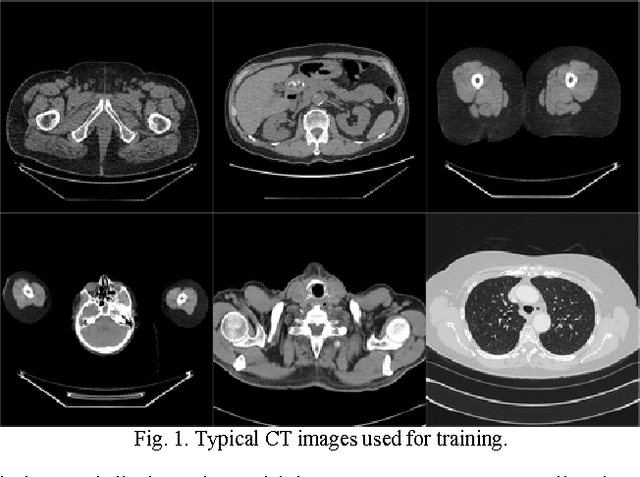

Abstract:Compressive sensing (CS) has proved effective for tomographic reconstruction from sparsely collected data or under-sampled measurements, which are practically important for few-view CT, tomosynthesis, interior tomography, and so on. To perform sparse-data CT, the iterative reconstruction commonly use regularizers in the CS framework. Currently, how to choose the parameters adaptively for regularization is a major open problem. In this paper, inspired by the idea of machine learning especially deep learning, we unfold a state-of-the-art "fields of experts" based iterative reconstruction scheme up to a number of iterations for data-driven training, construct a Learned Experts' Assessment-based Reconstruction Network ("LEARN") for sparse-data CT, and demonstrate the feasibility and merits of our LEARN network. The experimental results with our proposed LEARN network produces a competitive performance with the well-known Mayo Clinic Low-Dose Challenge Dataset relative to several state-of-the-art methods, in terms of artifact reduction, feature preservation, and computational speed. This is consistent to our insight that because all the regularization terms and parameters used in the iterative reconstruction are now learned from the training data, our LEARN network utilizes application-oriented knowledge more effectively and recovers underlying images more favorably than competing algorithms. Also, the number of layers in the LEARN network is only 12, reducing the computational complexity of typical iterative algorithms by orders of magnitude.

Abstract:To reduce the potential radiation risk, low-dose CT has attracted much attention. However, simply lowering the radiation dose will lead to significant deterioration of the image quality. In this paper, we propose a noise reduction method for low-dose CT via deep neural network without accessing original projection data. A deep convolutional neural network is trained to transform low-dose CT images towards normal-dose CT images, patch by patch. Visual and quantitative evaluation demonstrates a competing performance of the proposed method.